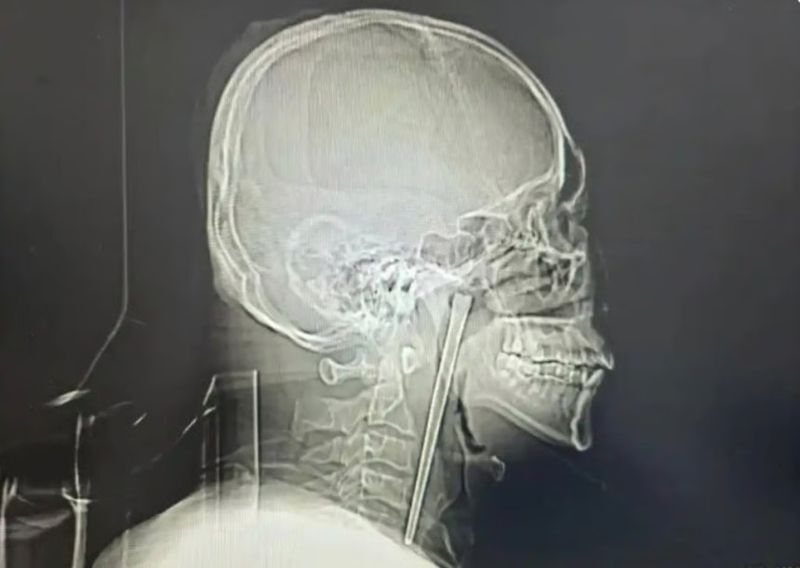

“숙취인 줄 알았지”…12㎝ 젓가락 목에 8년 꽂고 생활한 中 남성

목에 12㎝ 젓가락 박힌 채 8년... 中 남성, 뒤늦게 제거 수술한 사연